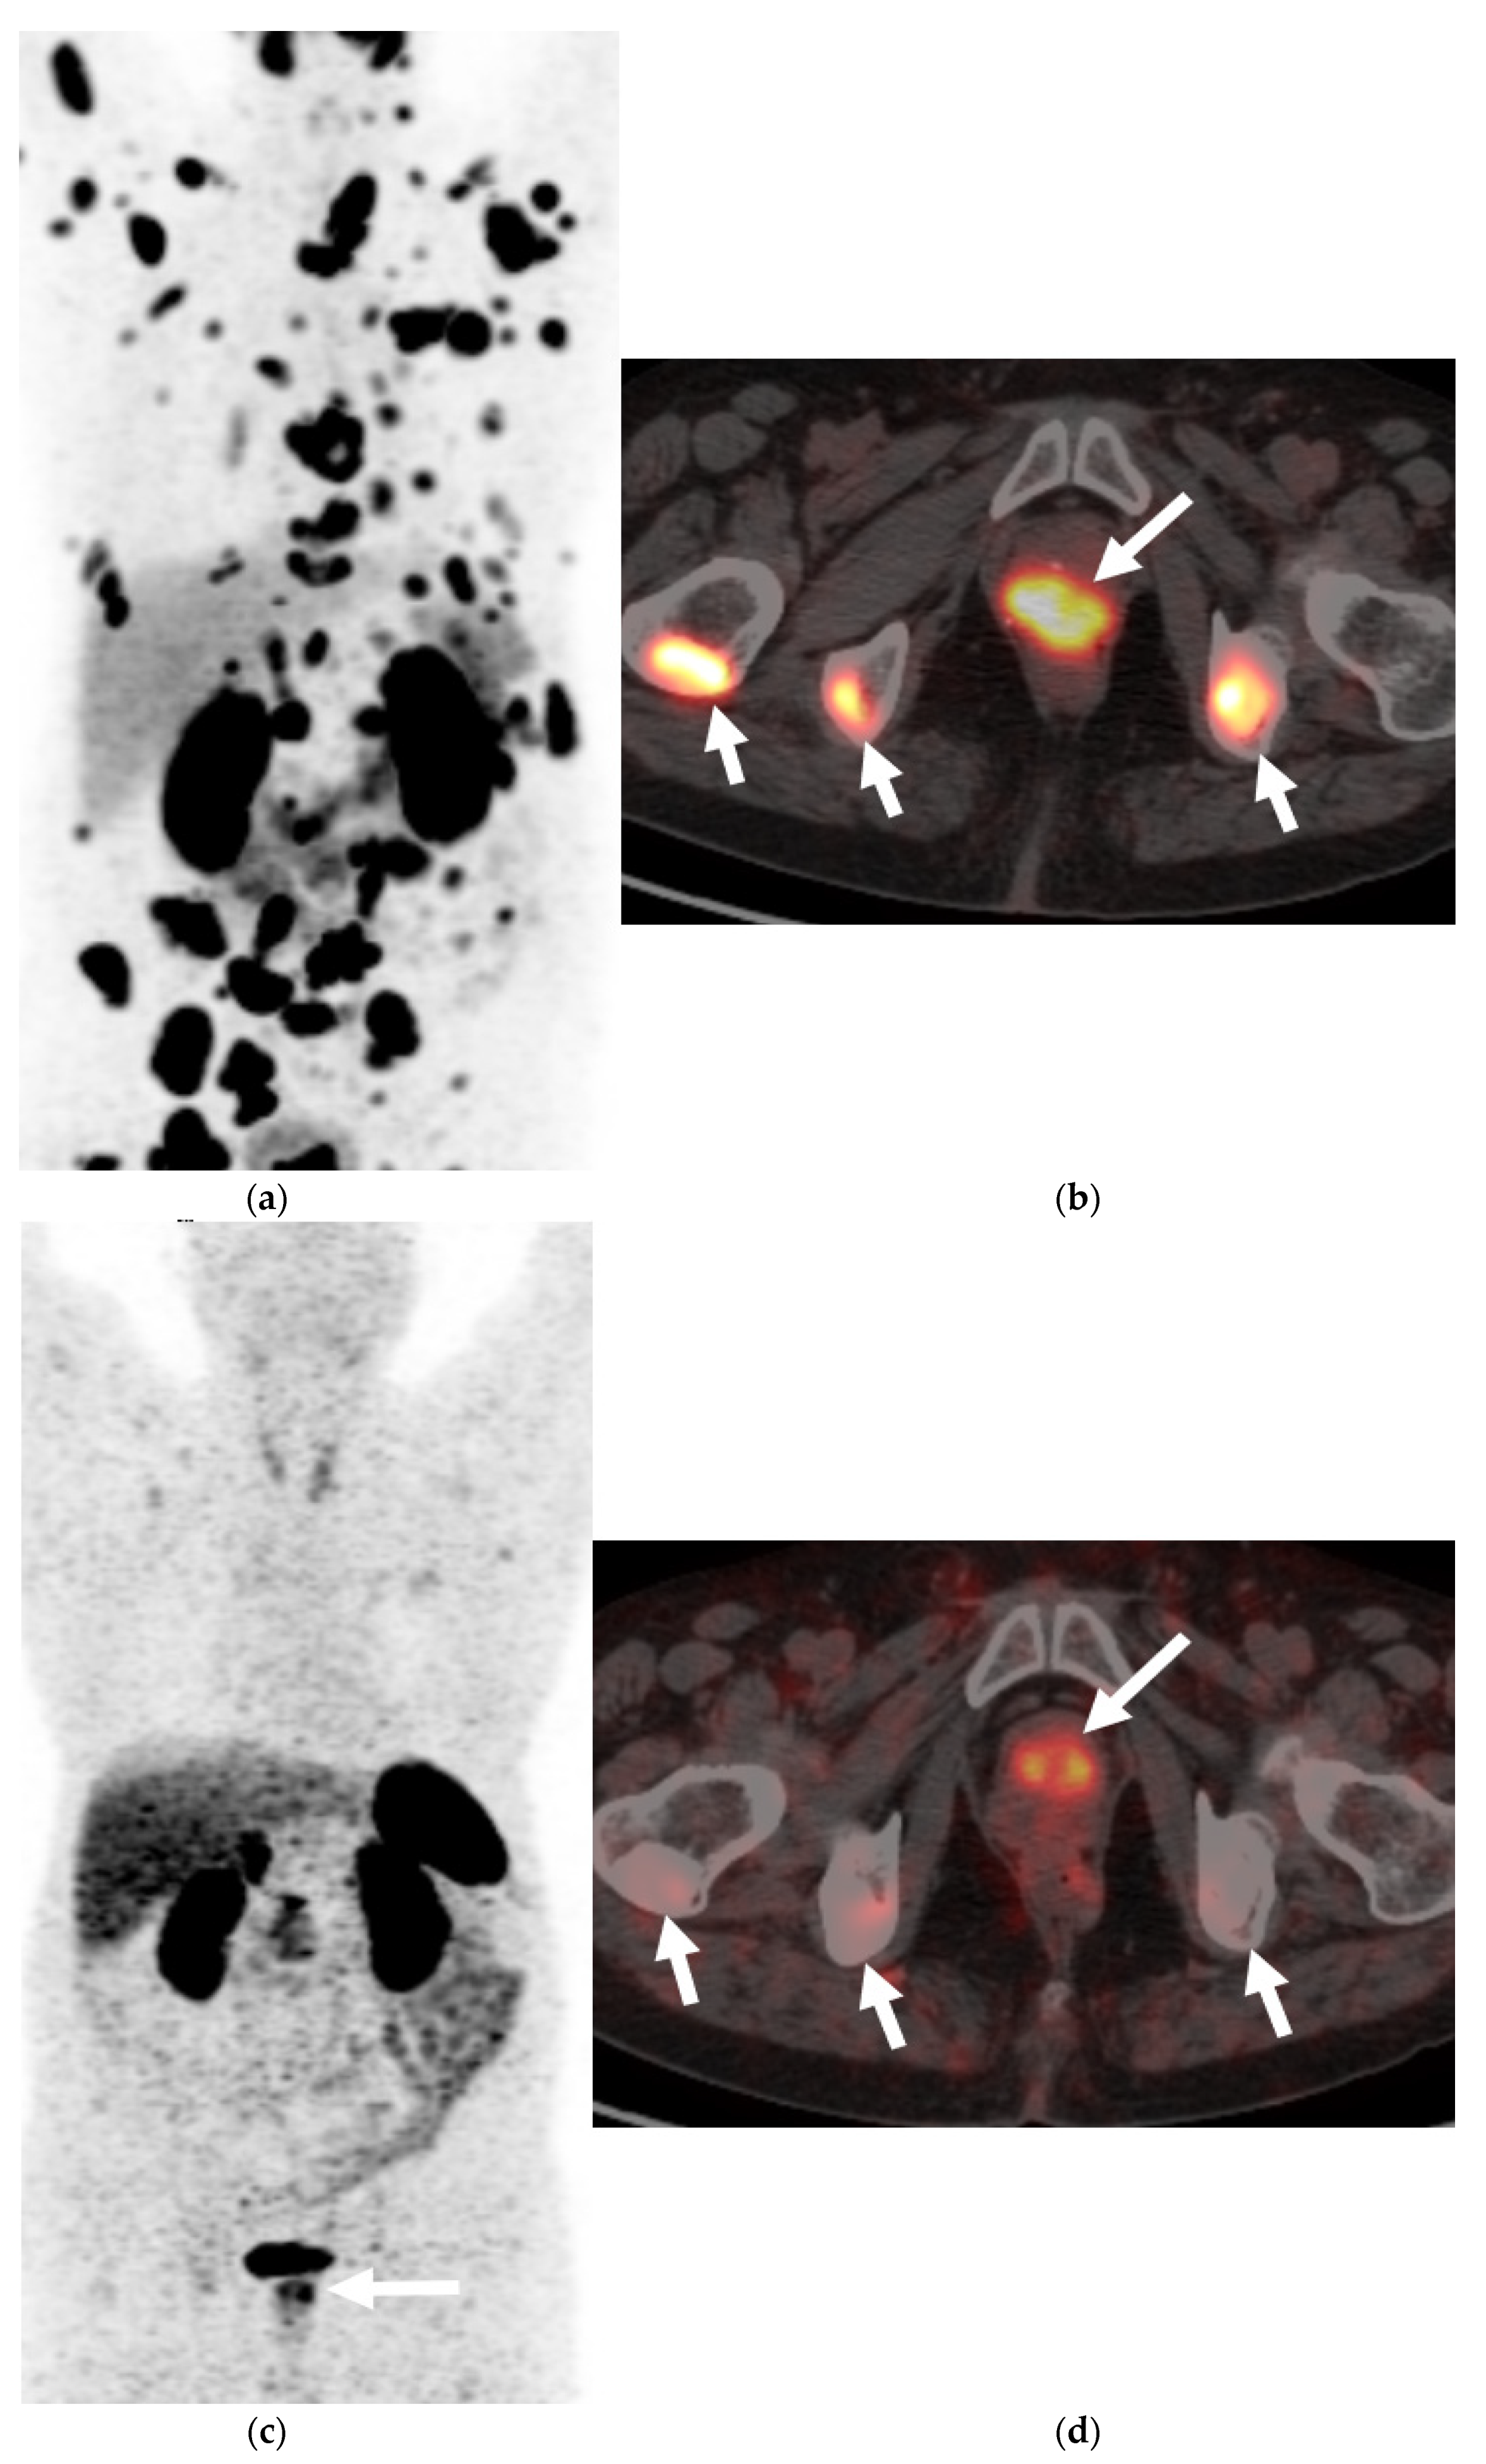

2.3.2. 68 Gallium Labelled Somatostatin Analogs (68Ga-DOTATATE or 68Ga-DOTANOC)

- Gofrit, O.N.; Frank, S.; Meirovitz, A.; Nechushtan, H.; Orevi, M. PET/CT with 68Ga-DOTA-TATE for diagnosis of neuroendocrine: Differentiation in patients with castrate-resistant prostate cancer. Clin. Nucl. Med. 2017, 42, 1–6. [Google Scholar] [CrossRef] [PubMed]

- Sharma, R.; Wang, W.M.; Yusuf, S.; Evans, J.; Ramaswami, R.; Wernig, F.; Frilling, A.; Mauri, F.; Al-Nahhas, A.; Aboagye, E.O.; et al. (68)Ga-DOTATATE PET/CT parameters predict response to peptide receptor radionuclide therapy in neuroendocrine tumours. Radiother. Oncol. 2019, 141, 108–115. [Google Scholar] [CrossRef] [PubMed]

- Santos, G.; Garcia, M.; Engler, H.; Alonso, O. Intraindividual comparison of 68Ga-DOTATATE PET/CT vs. 11C-choline PET/CT in patients with prostate cancer in biochemical relapse: In vivo evaluation of the expression of somatostatin receptors. Rev. Esp. Med. Nucl. Imagen Mol. 2018, 38, 29–37. [Google Scholar] [CrossRef]

- Usmani, S.; Ahmed, N.; Marafi, F.; Rasheed, R.; Amanguno, H.G.; Al Kandari, F. Molecular imaging in neuroendocrine differentiation of prostate cancer: 68Ga-PSMA versus 68Ga-DOTA NOC PET-CT. Clin. Nucl. Med. 2017, 42, 410–413. [Google Scholar] [CrossRef] [PubMed]